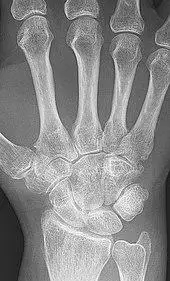

X-ray of the hand in rheumatoid arthritis.

X-rays of the hands and feet are generally performed when many joints affected. In RA, there may be no changes in the early stages of the disease or the x-ray may show osteopenia near the joint, soft tissue swelling, and a smaller than normal joint space. As the disease advances, there may be bony erosions and subluxation. Other medical imaging techniques such as magnetic resonance imaging (MRI) and ultrasound are also used in RA.[22][58]